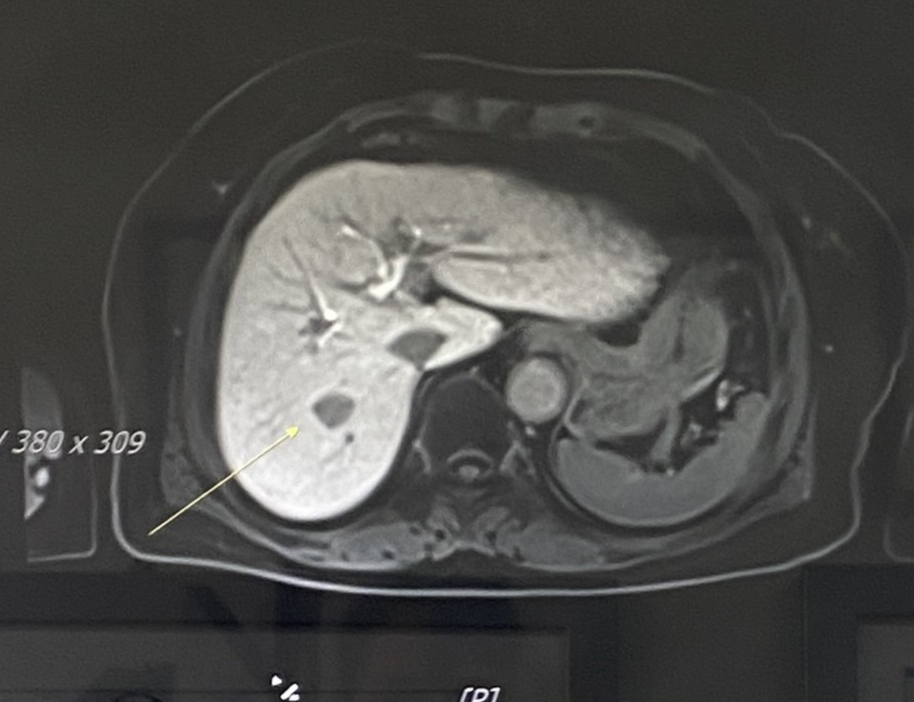

저희 어머니는 1개의 병변이 있었고 1.6m로 작았습니다. 그래서 이방법으로 시술을 했습니다.

위의 화살표의 표시된 부분이 1.6cm병번입니다.